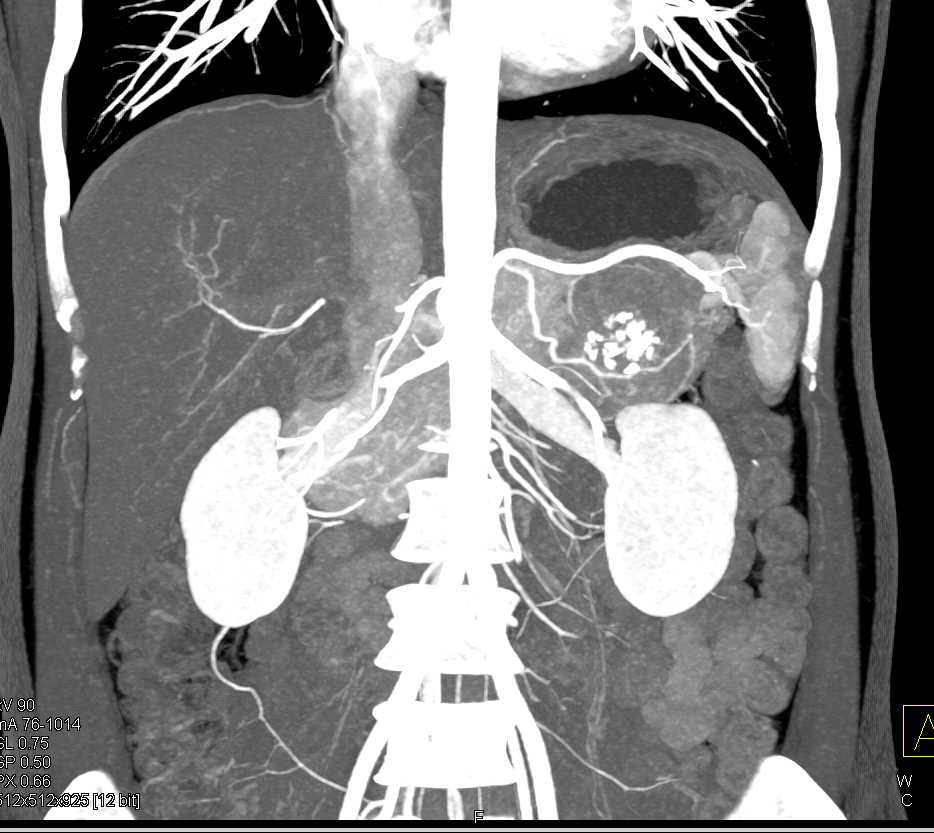

PNET Tail of the Pancreas